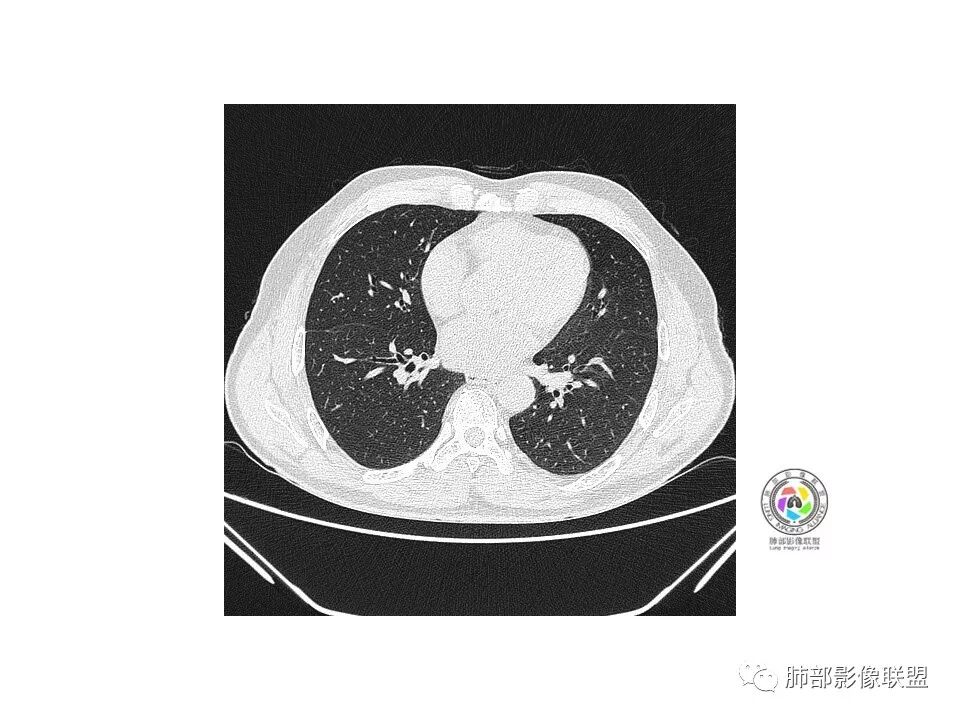

右肺下叶见边界清晰混合磨玻璃密度影,目测内见实性结节小于5mm,有浅分叶,前缘小叶间隔阻挡,月牙铲?胸膜牵拉,老年患者,MIA可能,鉴别炎性病变,抗炎后复查

患者老年男性,以咳嗽 、咳痰3天就诊,胸CT:右肺下叶前基底段mGGO,内可见血管形态改变,细支气管扩张,病灶边界清,边缘可见月牙铲。考虑恶性,腺癌?但建议先抗炎治疗后复查

右肺下叶混合磨玻璃结节,边缘清晰,浅分叶,月牙铲,胸膜牵拉,血管进入,考虑MIA可能,鉴别炎性病变

患者老年男性,咳嗽  咳痰3天就诊。胸部CT:右肺下叶前基底段混合磨玻璃结节,边缘清楚,可见毛刺、胸膜牵拉、血管集束、月牙铲征象。综合考虑微浸润腺癌可能大。

右肺下叶前基底段混合磨玻璃结节,边界清,浅分叶,胸膜牵拉,月牙铲,血管进入,考虑:微浸润腺癌可能性大,抗炎后复查。

老年男性,咳嗽、咳痰3天。胸部CT:右肺下叶前基底段mGGN,边缘清楚,内可见不规则实性成分,病灶可见空泡、毛刺、胸膜牵拉、血管集束征象。考虑MIA可能大,抗炎2W后复查。

老年男性,右下肺前基底段混合GGN,边缘清晰,月牙铲,叶间胸膜牵拉,有轻度收缩力。结合病史抗炎2-3周后复查,消失考虑炎症,变化不大为腺癌。本例总体支持腺癌

老年男性,咳嗽3天,右肺下叶前基底段混合磨玻璃结节,形态不规整,相邻胸膜凹陷,可见血管影,考虑腺癌可能性大,不除外炎症可能,建议抗炎1~2周,1个月复查胸部CT。

右肺下叶mGGN,内部结构紊乱,可见小点状高密度影,边缘清晰,小叶间隔阻挡,轻度收缩力,考虑MIA,常规飞一会20天复查。

老年男性,右肺下叶前基底段GGN,界清,内部血管结构杂乱,叶间胸膜牵拉。考虑恶性,早期腺癌可能,建议抗炎治疗后复查对比。

右肺下叶前基底段见一磨玻璃结节影,呈分叶状,边缘部分模糊,与胸膜间有长条索粘连,内有增粗的血管影,后者边缘毛糙,考虑微浸润性腺癌,建议抗炎治疗后复查

老年男性,右肺下叶前基底段斜裂旁可见单个混合型磨玻璃结节mGGN,边缘清,内部结构紊乱,进入的血管增粗,支气管关系不好判断,斜裂侧可见牵拉,常规考虑微侵腺癌MIA,建议先抗炎后复查及手术干预。

老年男性,咳嗽咳痰3天。MGGN,边缘见月牙铲、胸膜牵拉,血管移动联通?冠状位隐约可见支气管穿行,考虑MIA,重建冠位可见结节比较靠近叶裂,可积极手术处理。

老年男性,右S8混合磨玻璃结节,边缘尚清晰,局部凹陷,叶间胸膜牵拉,考虑MIA可能大,建议抗炎治疗10天,6-8周后复查

右肺下叶混合磨玻璃密度结节,有月牙铲,内可见血管,血管移动联通,常规消炎复查,还存在考虑AIS-MIA

患者老年男性,右下肺前基底段靠近胸膜侧可见一个mGGO结节,边缘清淅,可见分叶征及月牙铲,小结节病灶胸膜牵拉明显,首先考虑MIA可能性大。

右肺下叶mGGO,边缘清晰,浅分叶,内血管影增粗,见点状实性成分,小支气管牵拉扩张,考虑MIA,建议抗炎后复查。

右肺下叶前基底段mGGN,边界清晰,内部结构杂乱,见网格空泡感,月牙铲,浅分叶及胸膜牵拉,倾向MIA。

右肺下叶GGO,边缘清晰,有月牙铲,有血管进入,内部结构紊乱,胸膜牵拉,考虑MIA,常规建议抗炎治疗后复查。

右肺下叶磨玻璃结节,边界清晰,边缘有分叶及月牙铲,并可见轻度胸膜牵拉,收缩力弱,有血管移动联通征,而且病灶内血管影轻度增粗,实性成分很少,考虑AIS,可以让子弹再飞一会,或常规抗炎治疗后复查。

右肺下叶前基底段磨玻璃小结节,其内血管稍增粗,边缘见分叶、月牙铲,考虑ais,炎性结节不排